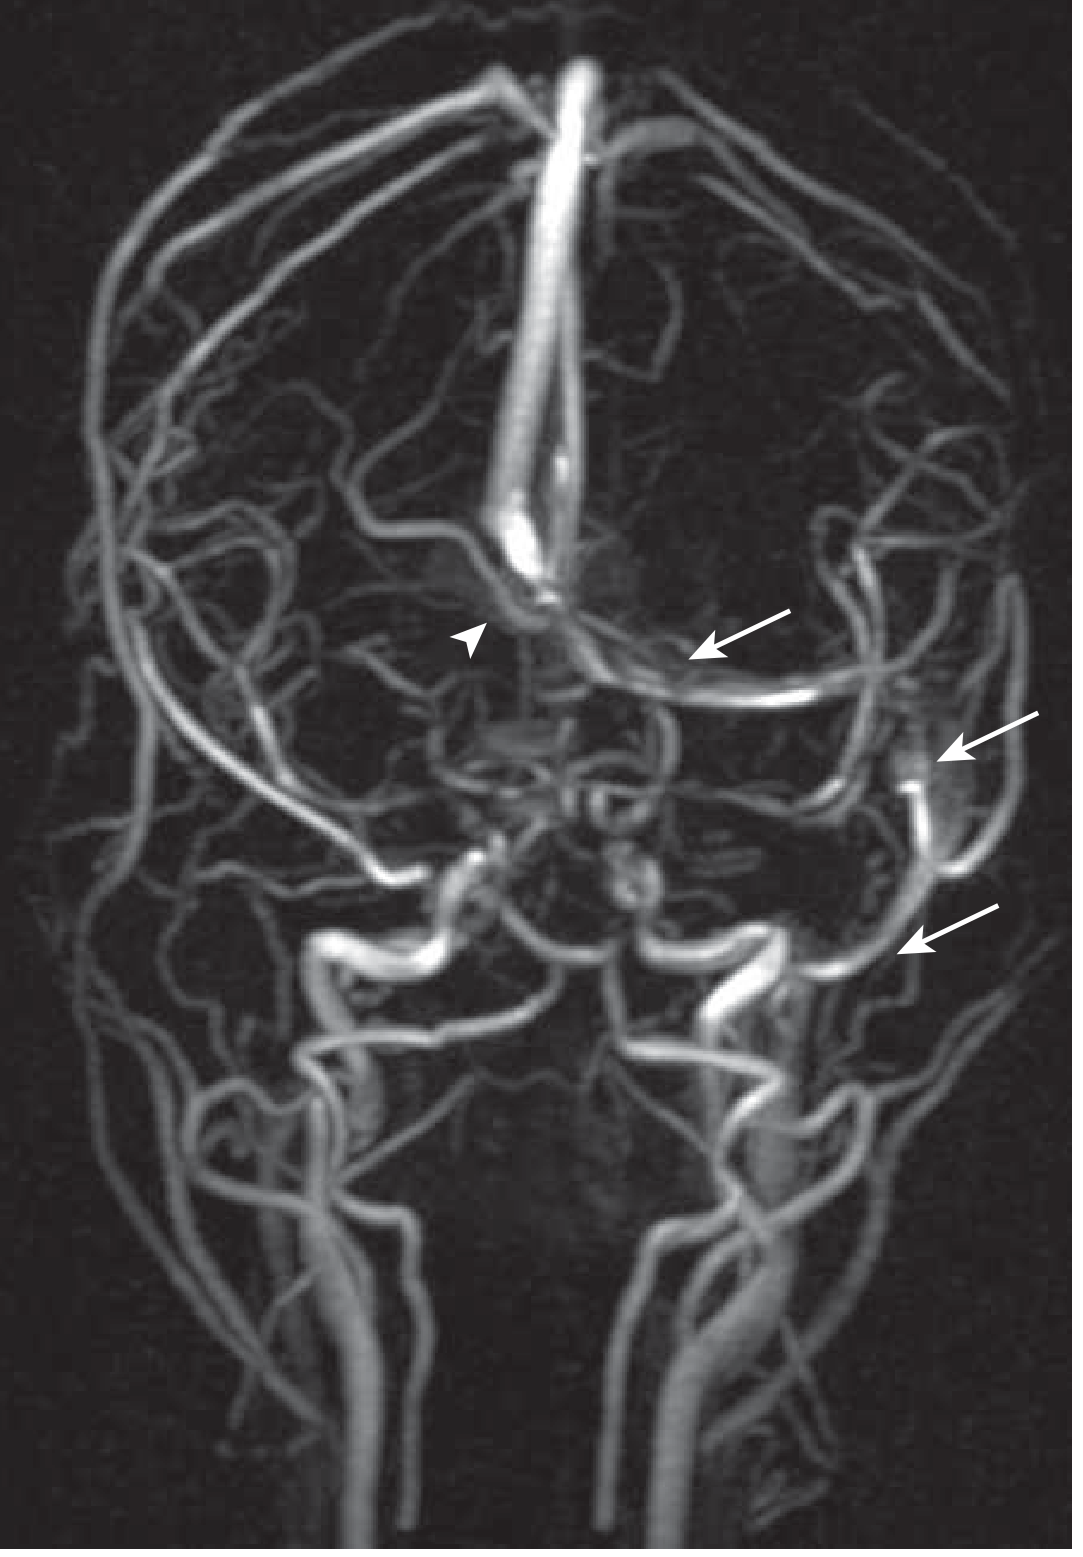

Fig. 3 — MR Venogram: absent flow in the right transverse and sigmoid sinus (arrowhead) with intact left-sided flow (arrows)

MR venogram showing right transverse sinus thrombosis

MR venogram: absent flow in right transverse sinus (arrowhead) and sigmoid sinus; intact left-sided flow (arrows). — Goldman-Cecil Medicine, Fig. 376-6